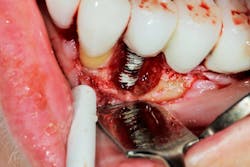

Another scenario that took place in a private practice with actual dollar amounts can be seen in treatment plan C. This patient had already paid for treatment plan B in the $5,000–$7,000 range and subsequently presented to the practice with moderate peri-implantitis. In addition to the money the patient had already invested, she would now be responsible for the financial costs of treatment plan C.

After reviewing the additional costs and lengthy healing time involved with surgery to correct the ailing implant, the overall costs associated with treatment were in the $8,000–$10,000 range, with more than three years of treatment time invested. Of important note is that most insurance companies limit the amount of reimbursement for implant-related services. When dealing with insurance companies, accurate ADA coding and claims submission are critical to facilitate services and expedite reimbursement.